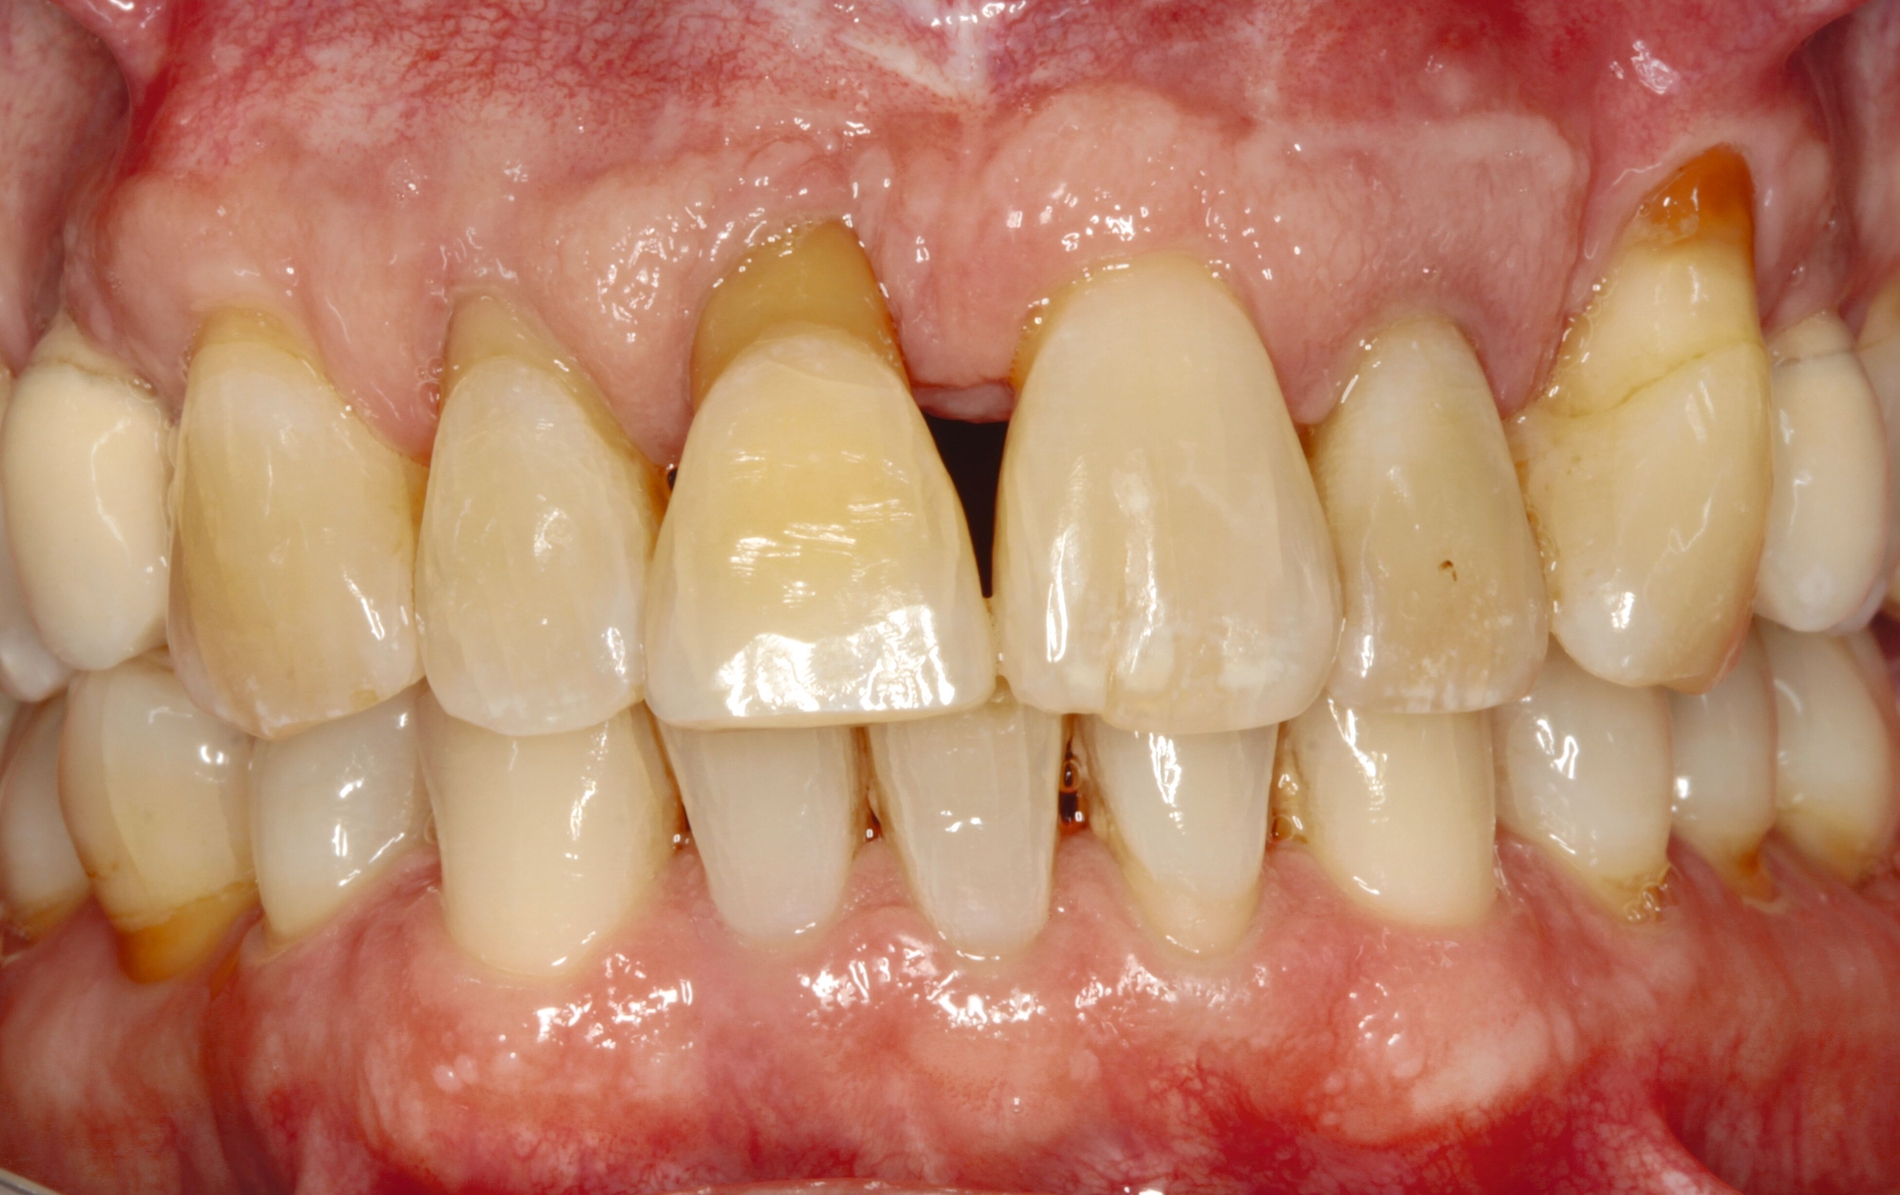

Möglichkeiten zur Therapie des okklusalen Traumas sind das selektive Einschleifen okklusaler Frühkontakte, die Schienung der betroffenen Zähne oder gegebenenfalls auch kieferorthopädische Bewegungen der Zähne sowie eine Kombination der genannten Therapieformen [Fan und Caton, 2018; Dommisch et al., 2022]. Ein Beispiel für eine Schienung bei Vorliegen einer okklusalen Dysfunktion ist in Abbildung 2 dargestellt.